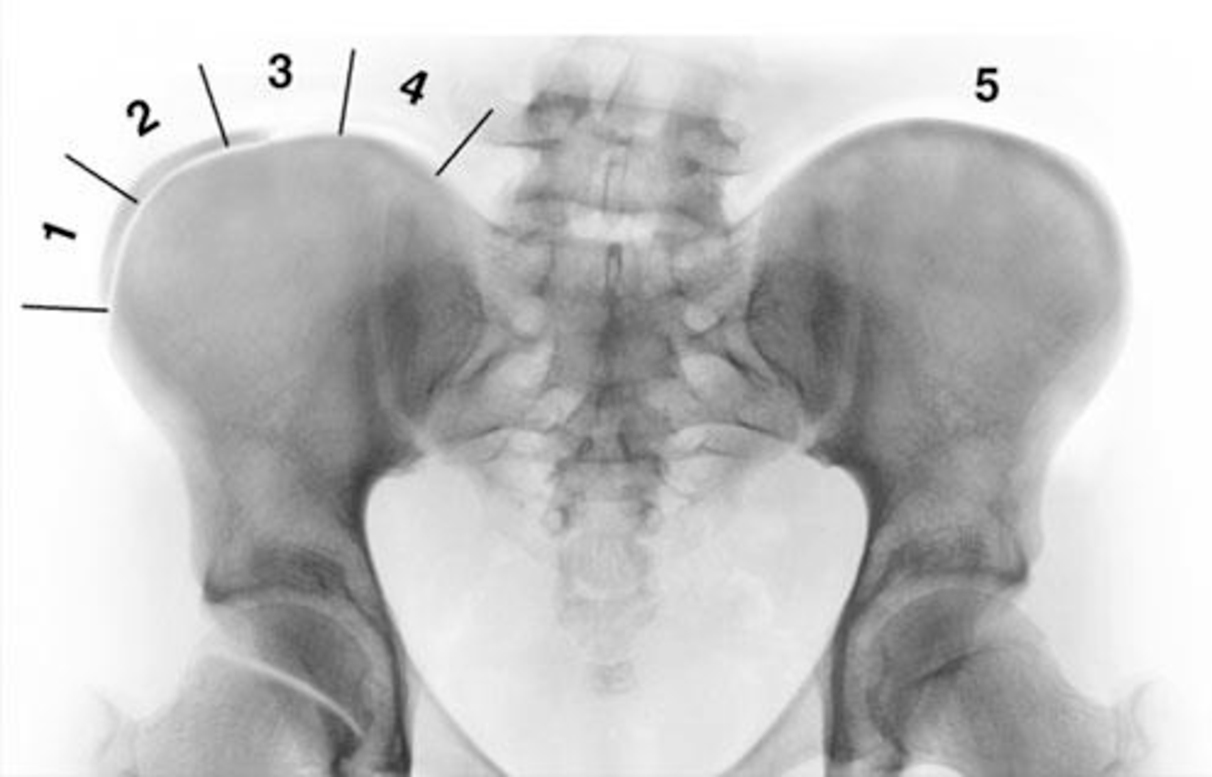

IL GRADO RISSER

Il grado di Risser descrive una fase della maturità scheletrica basata sull'osservazione dello stadio di ossificazione della cresta iliaca. Il processo di ossificazione inizia dalla porzione più laterale dell'apofisi iliaca e prosegue fino alla completa fusione dell'intera cresta iliaca.

Sebbene il grado di Risser sia ancora ampiamente utilizzato dai clinici, tale strumento diagnostico non fornisce alcuna informazione sulle fasi iniziali dello sviluppo. Il centro di ossificazione, infatti, si osserva inizialmente verso la fine del picco di crescita.